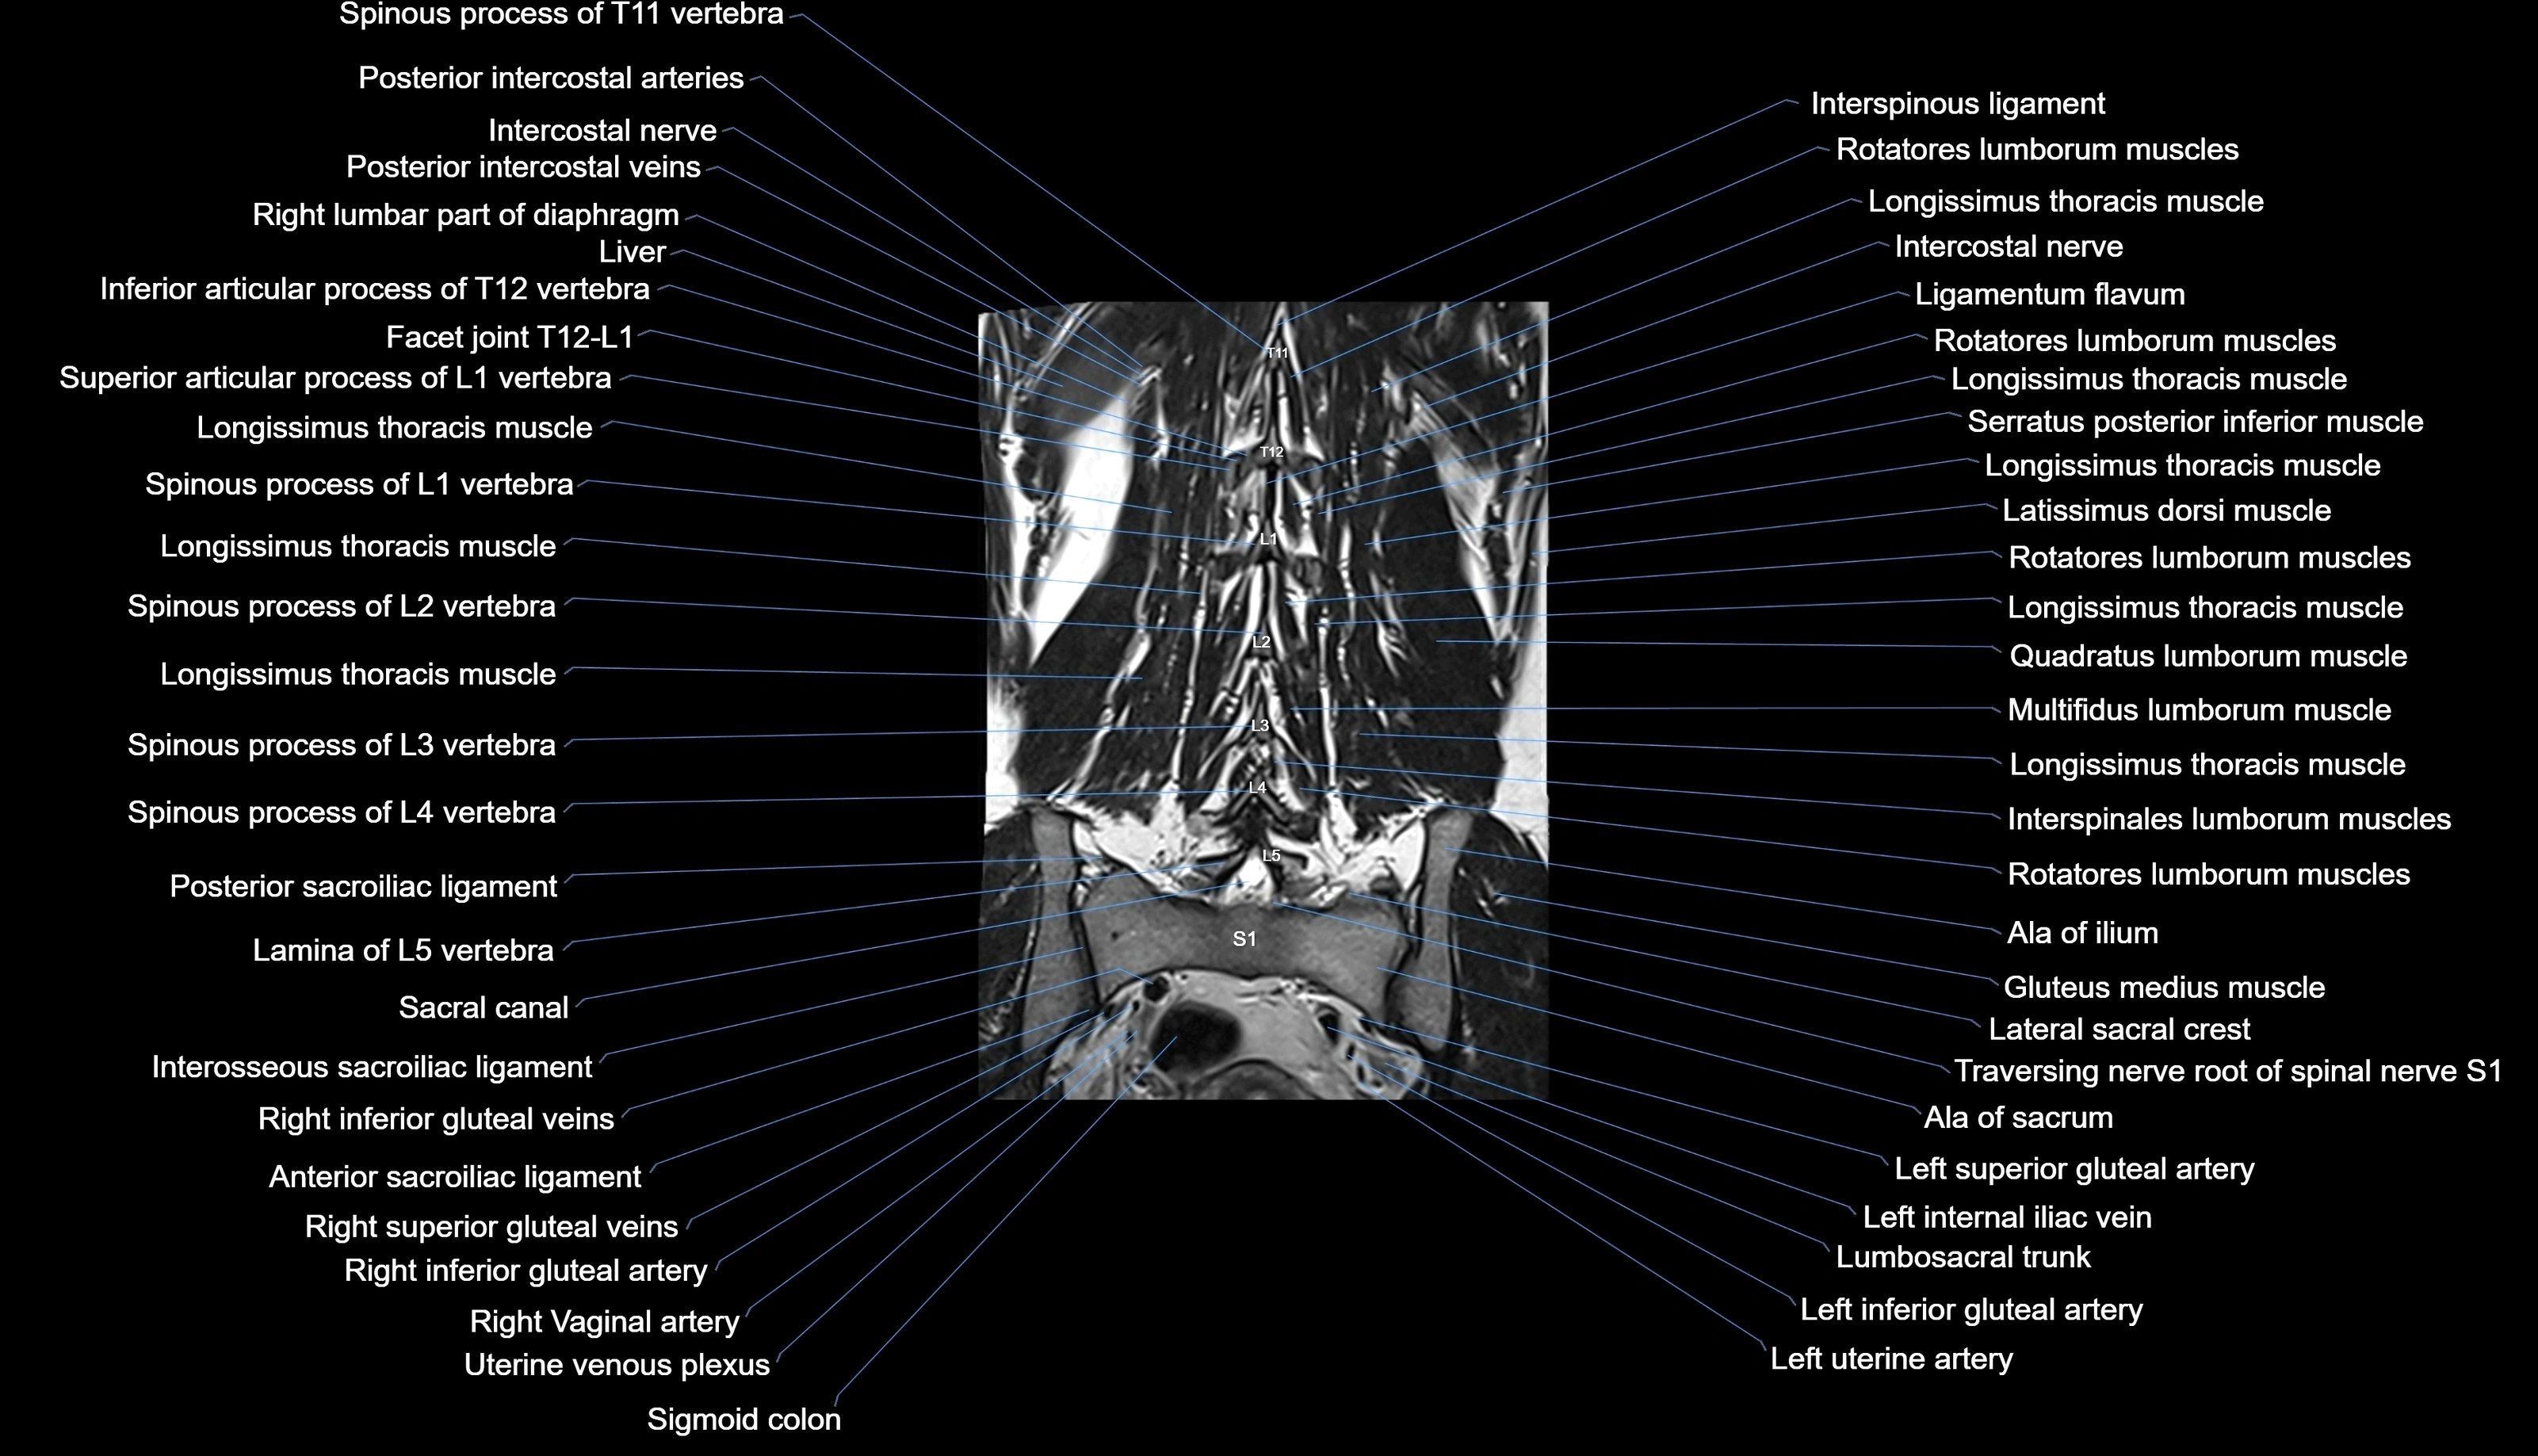

MRI images